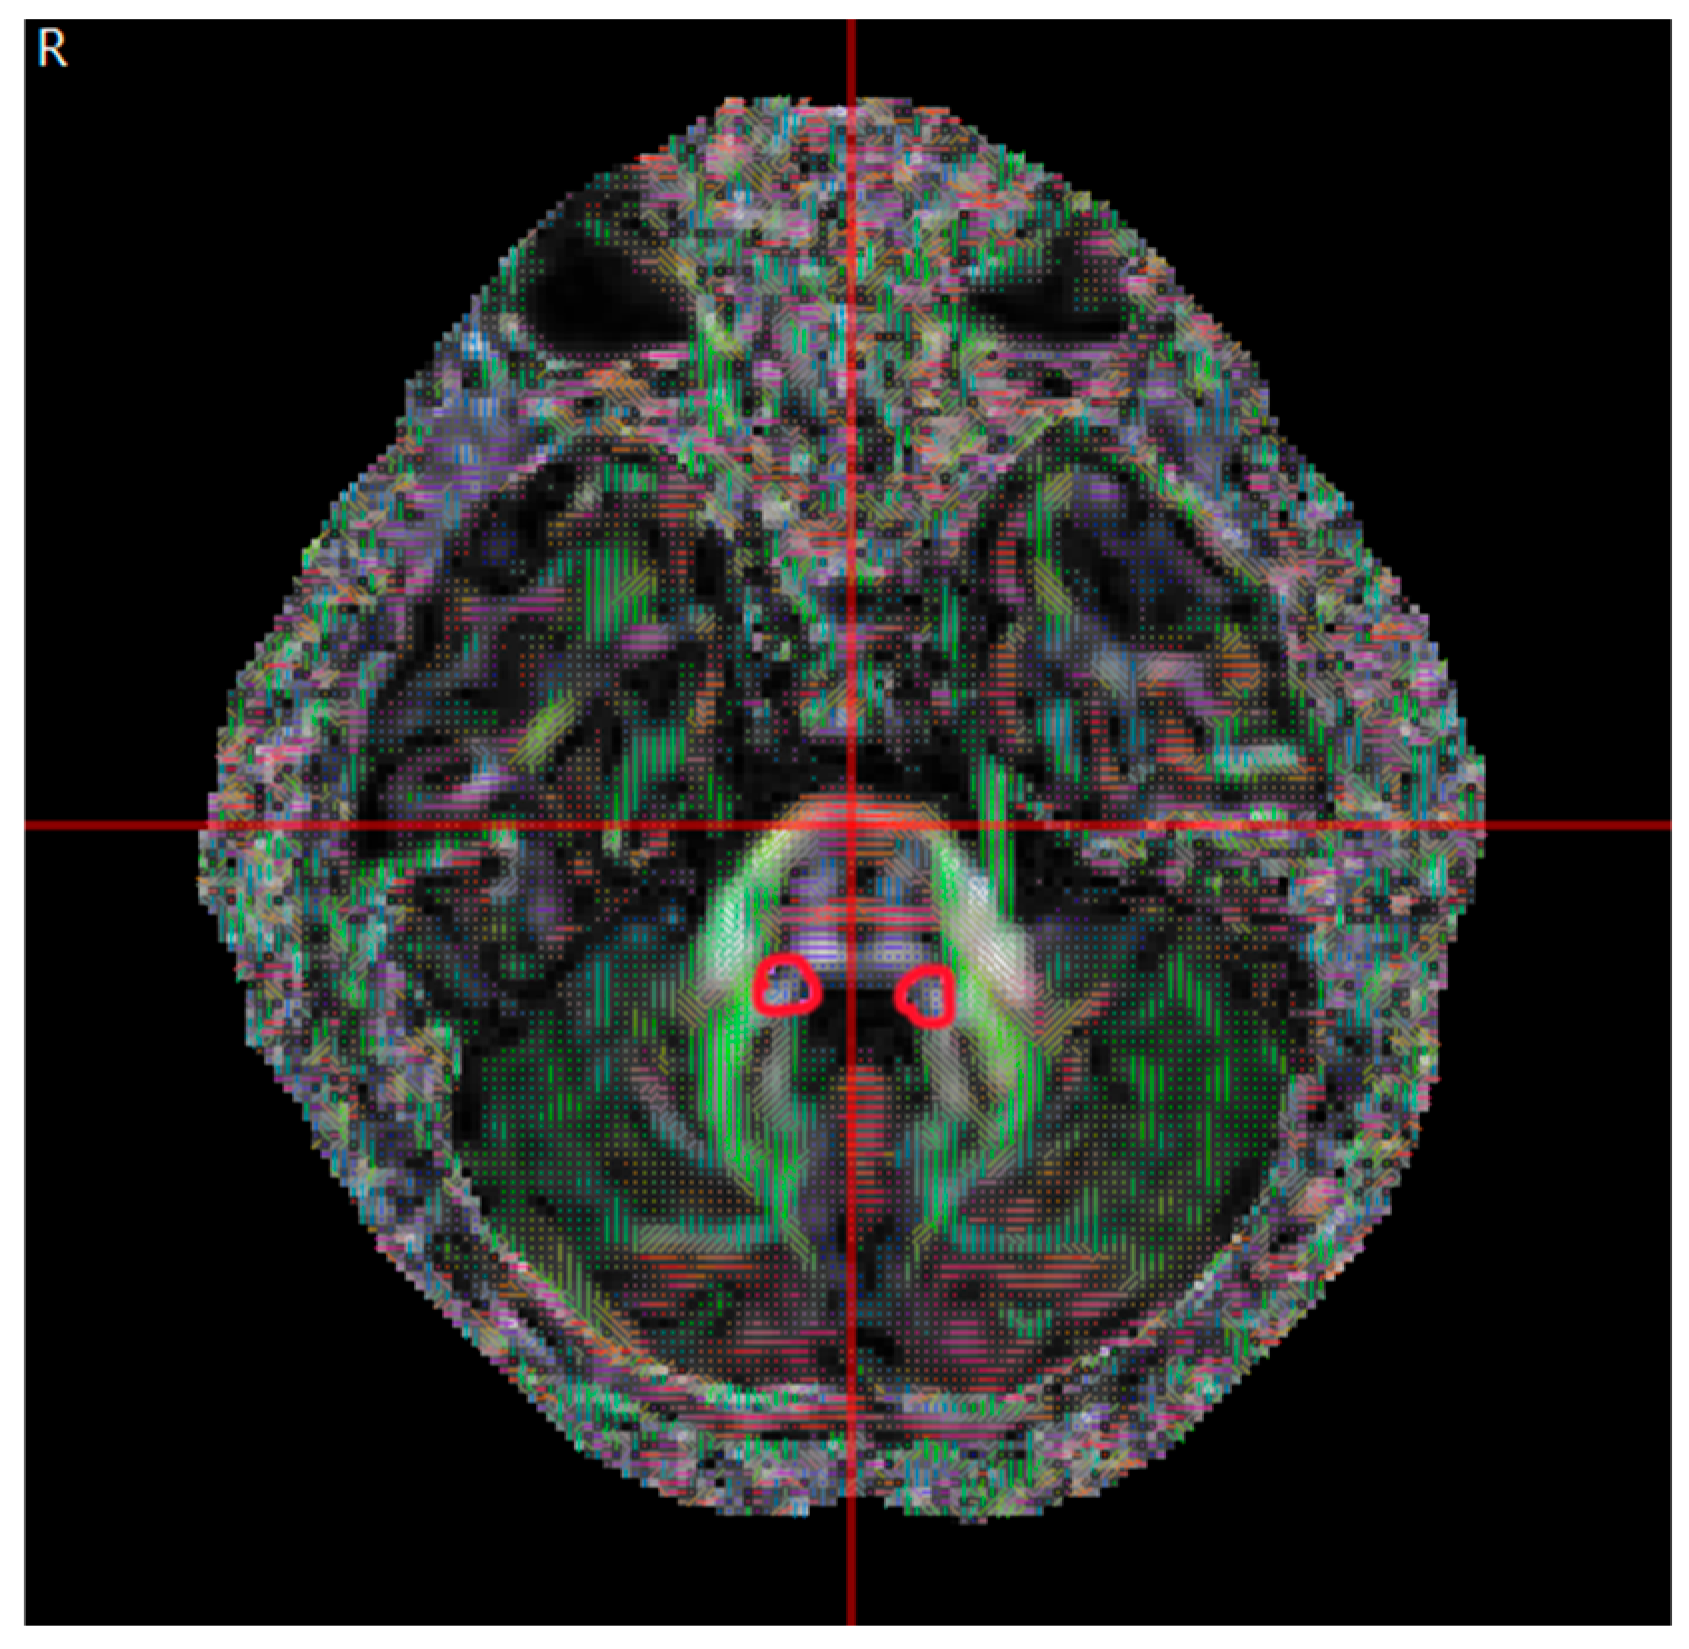

2.2. Data Collection

2.3. Basic Theory of DTI Metrics

2.4. Data Analysis